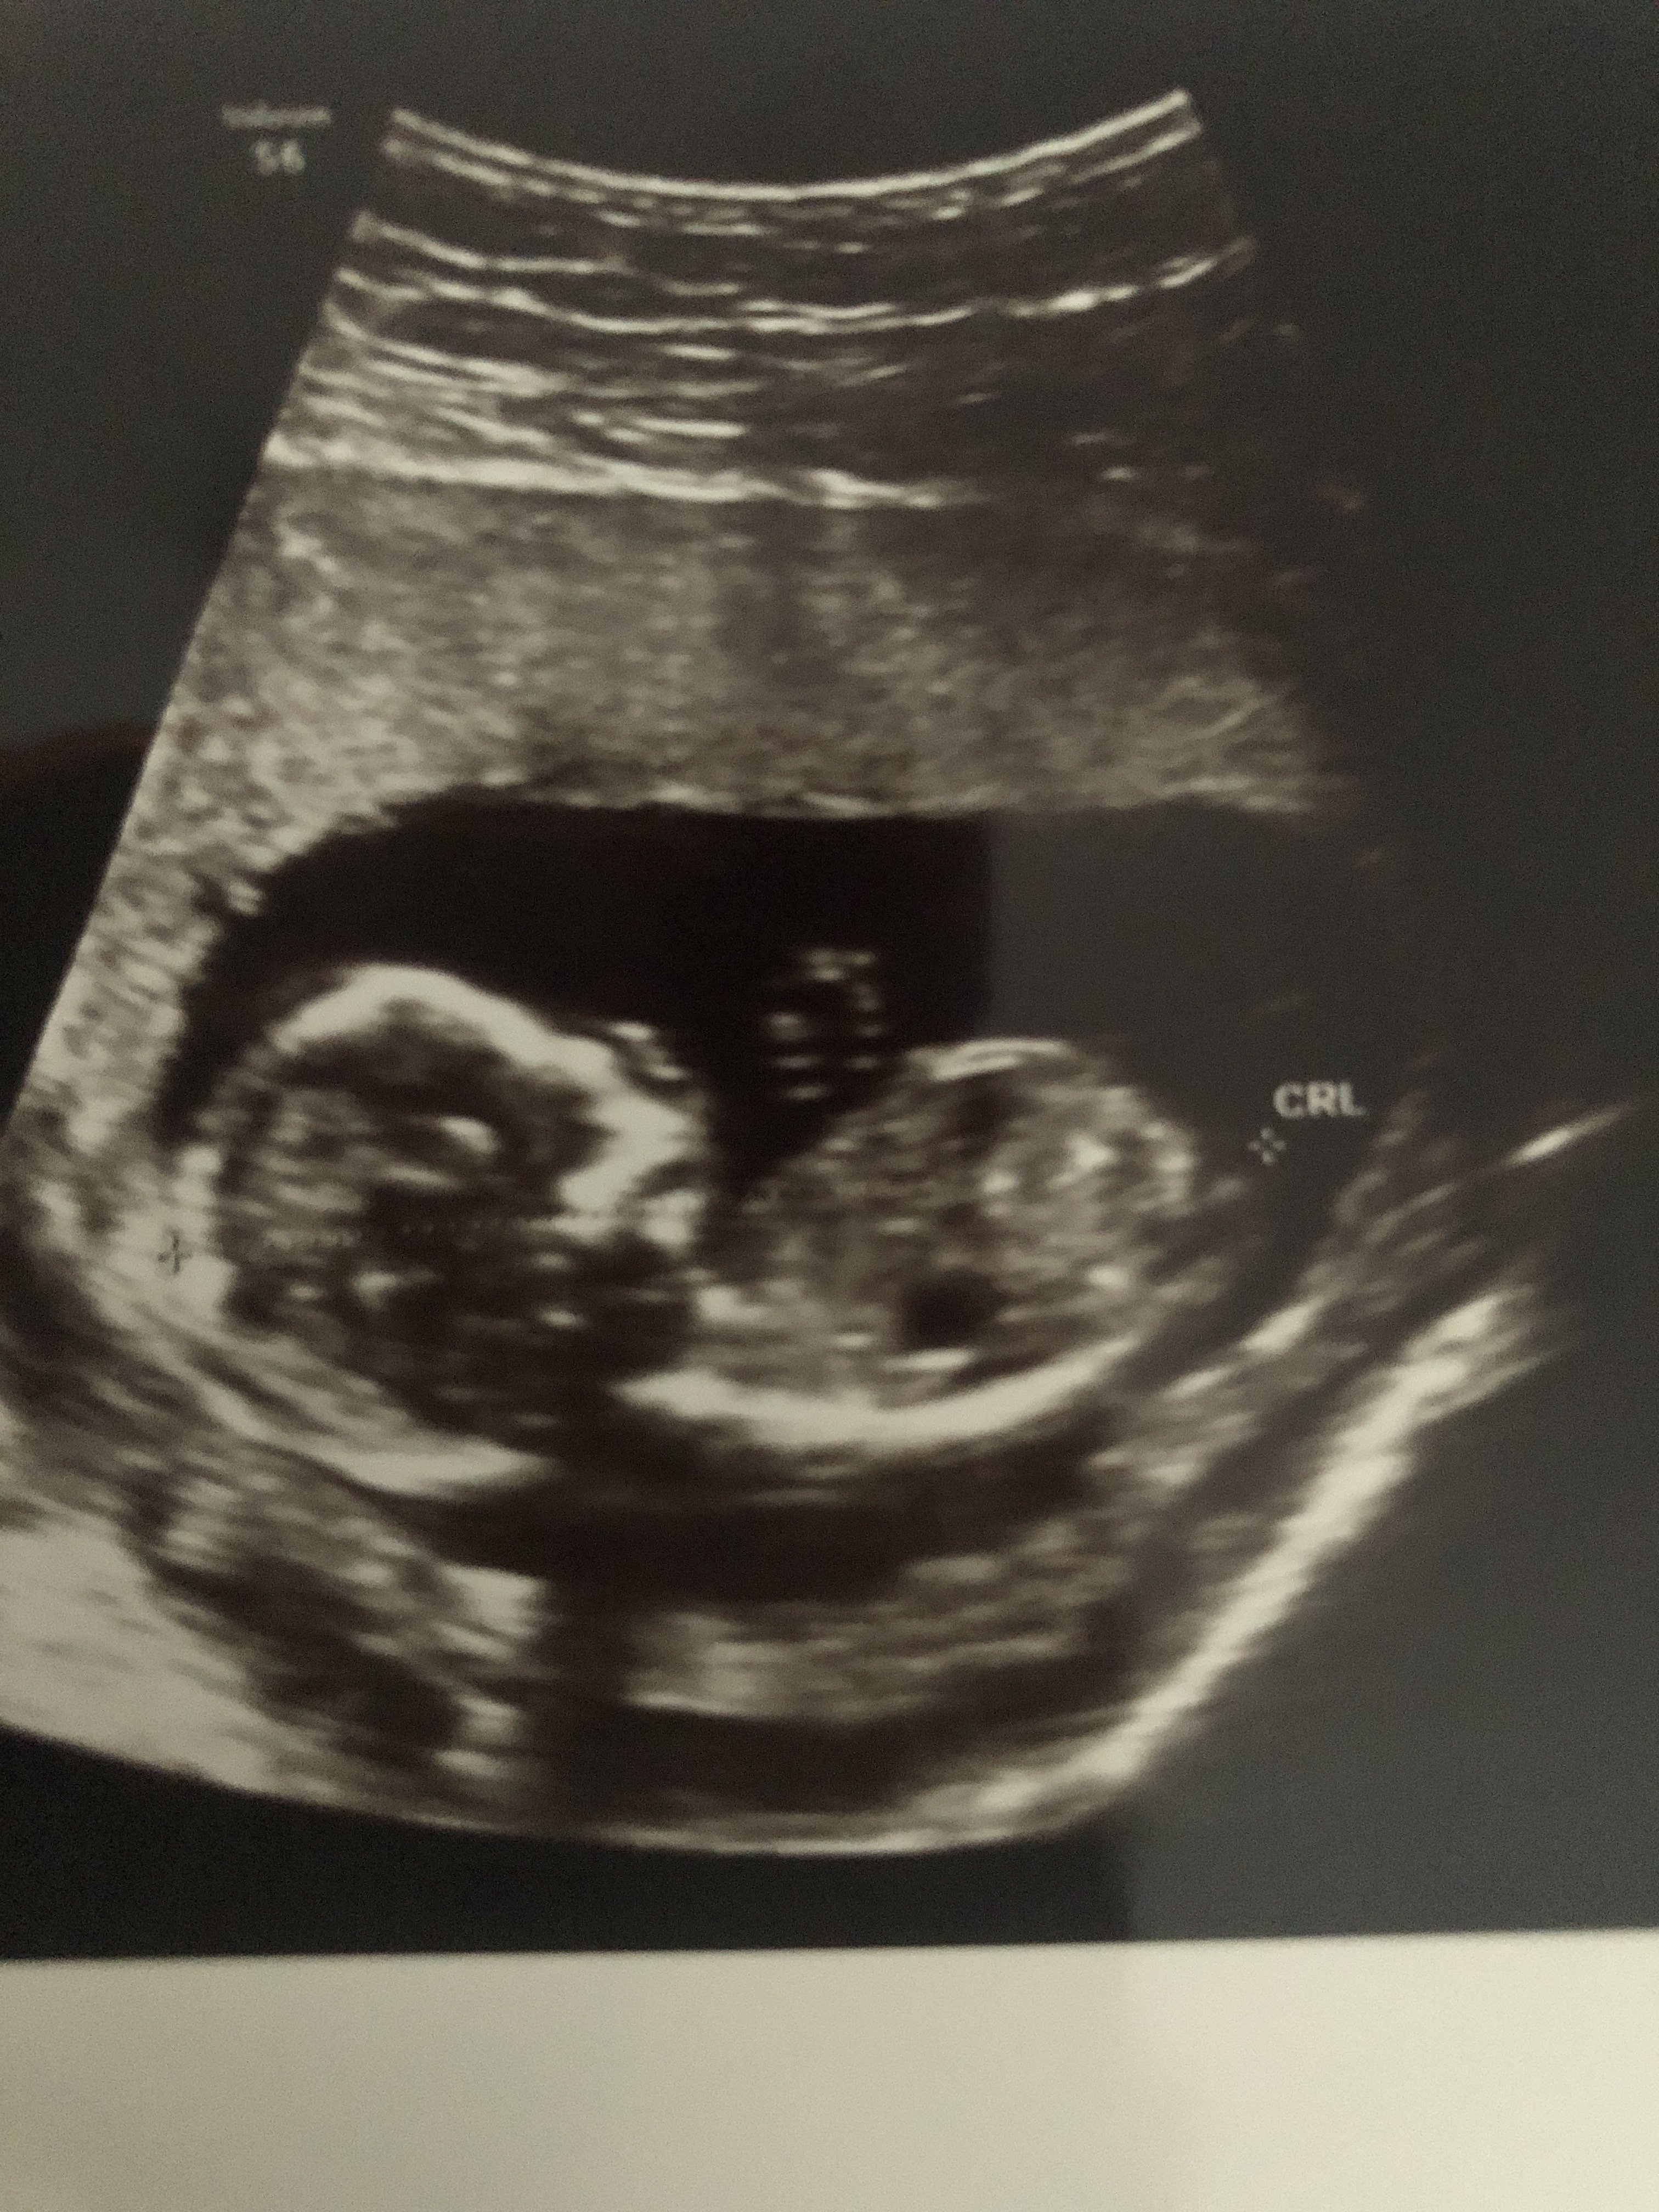

Witam w 19 tygodniu ciąży dowiedziałam się ze będę miała dziewczynkę w 20 tyg okazało się jednak , że to chłopak. Sama już nie wiem bo na jednym usg widać na pewno dziewuche a na drugim chłopca. Może to pempowina ?? Może ktoś mi pomoże rozwiązać ta zagadkę